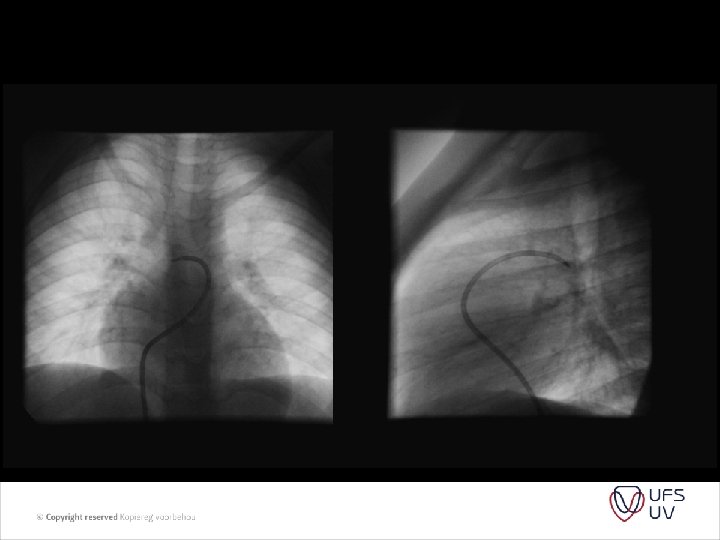

• Caption: Picture 4. Pulmonary artery banding. Circumferential banding of a dilated pulmonary artery can acutely lead to internal infolding of the arterial wall. Later resorption of the infoldings and remodeling of the arterial wall restore a greater internal crosssectional area.

HOW TIGHT SHOULD THE BAND BE? • Trusler formula - early 1972 • A method of banding the pulmonary artery for large isolated ventricular septal defect with and without transposition of the great arteries. Trusler GA, Mustard WT. I - noncyanotic nonmixing lesions - 20 mm + 1 mm/kg II - Mixing lesions (TGA+VSD) - 24 mm + 1 mm/kg III - Single ventricle for Fontan - 22 mm + 1 mm/kg

• Intra-op pressure and saturation monitoring , aim to lower PAP to normal or ½ of systemic without desaturation or bradycardia - many variable factors - GA - Mechanical ventilation - Open chest - Days after op when hematocrit / p. H ext. • Determine Qp/Qs after Trusler formula was used. • Site of placement – mid MPA trunk